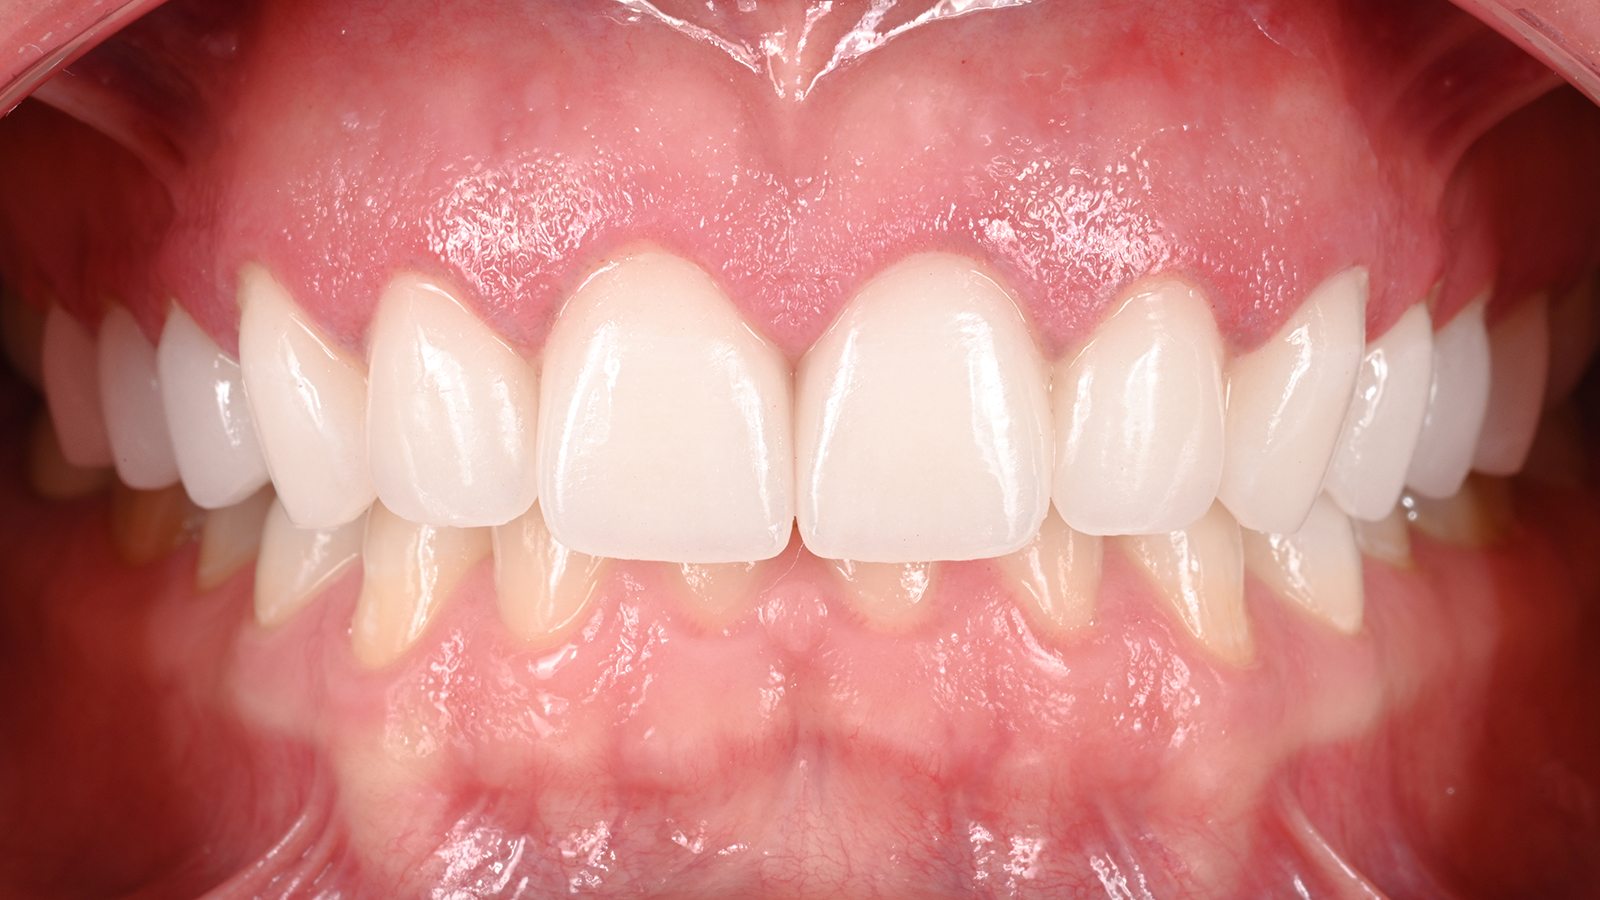

The good news is that modern extraction techniques, combined with sedation options and our advanced technology, make the procedure far more comfortable than you might expect. Following your extraction, we'll discuss the best tooth replacement options to restore both the function and aesthetics of your smile.

After